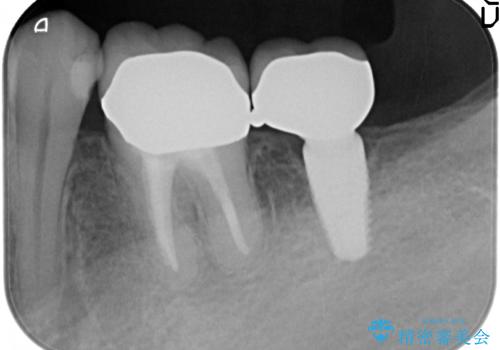

- 虫歯を放置し他院で抜歯後、入れ歯を提案されインプラント治療を希望され来院されました。

CT画像より骨の量は少なくそのままではインプラントの埋入が難しい状態です。

骨造成を行い安定したインプラントの環境を整える治療を計画します。